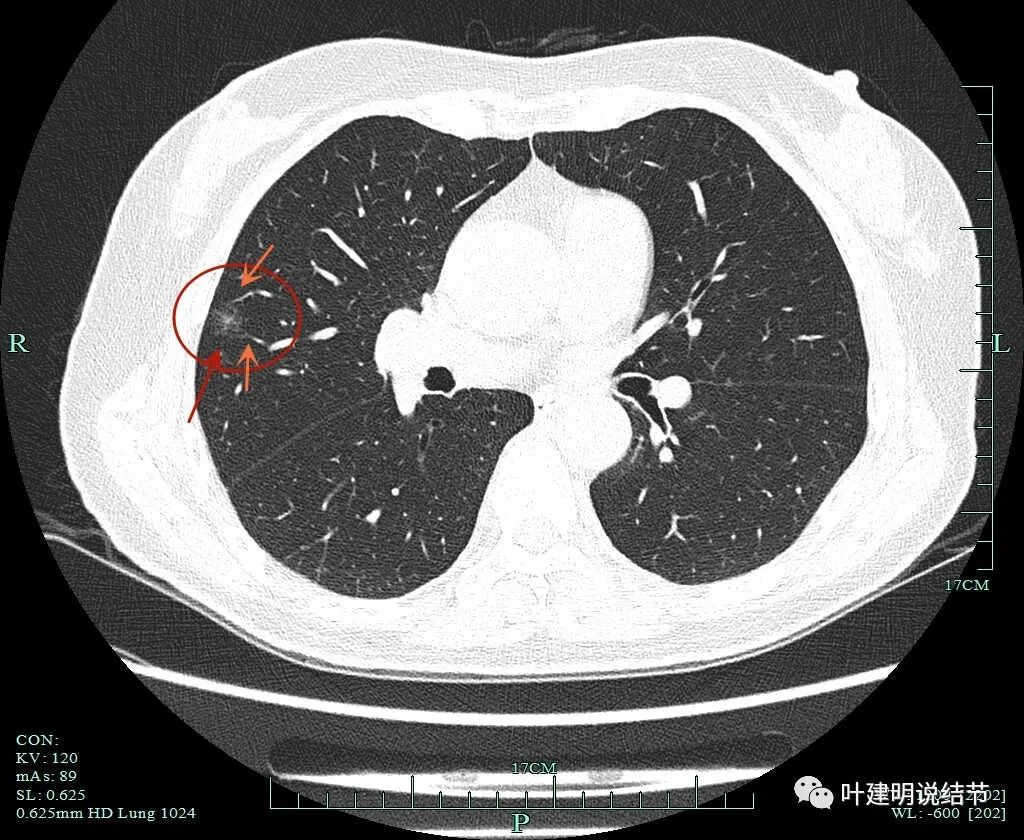

病灶8:右下叶磨玻璃结节了,轮廓清,血管贴边,边缘显毛糙。

有明显小血管进入,小血管有异常增粗。从密度考虑不典型增生可能性大,但因血管进入升一级考虑,原位癌可能性大点。如果没有上叶病灶6存在,此灶可随访,近期风险不算高。

病灶8重建后显示血管与结节间没有间隙,而且瘤肺边界很清。

病灶9的重建发现不是实性结节,而混合磨玻璃密度。绿色箭头示边上有磨玻璃成分,而且紫色箭头示边缘是毛糙的,红色箭头示整体轮廓是清的。

上图也显示病灶边缘毛糙,不光滑,与胶原结节、淋巴结等良性结节是不符合的。

影像再判断:

右肺中叶病灶9考虑是浸润性腺癌,比其他病灶风险都高,它应该是主病灶了。但鉴于两肺多发病灶基本上都考虑肿瘤范畴的,即使此灶考虑浸润性,但毕竟还小,也有磨玻璃成分,存在转移的概率极小,仍应该可以考虑妥协性的楔形切除。